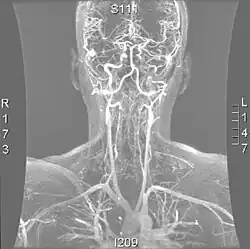

- delikatność i kruchość narządów (np. jelit – IBS, pęcherza – nadmierna rozciągliwość ścian pęcherza i/lub neurogenny pęcherz, naczyń krwionośnych – niewydolność naczyń krwionośnych, POTS, żylaki);

- może dojść do pęknięcia dużych naczyń krwionośnych oraz narządów (głównie w typie vEDS);